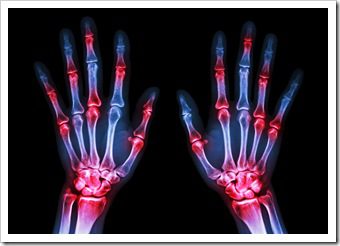

The joints of our knees and the leg pains associated can be confusing or frightening sometimes when we hear the medical diagnosis. The actual diagnosis terms can sometimes be more scary than the actual condition. But do not fear! Below are two common conditions explained simply so that you can begin focusing on the solution...